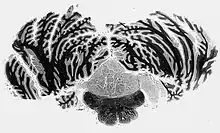

They are classically found within the fourth ventricle, typically have a well demarcated interface to normal tissue and do not usually extend into the brain parenchyma, like ependymomas often do.[4]

On a CT, it often shows a less dense to equally dense mass. If it is big, it may have parts that are cystic or calcific.[2] In 50-60% of cases, the tumor is in the fourth ventricle, while the second most common (30-40% of cases) location is the side ventricles. It is rare for it to be in the third ventricle or the central canal of the spinal cord.[2]